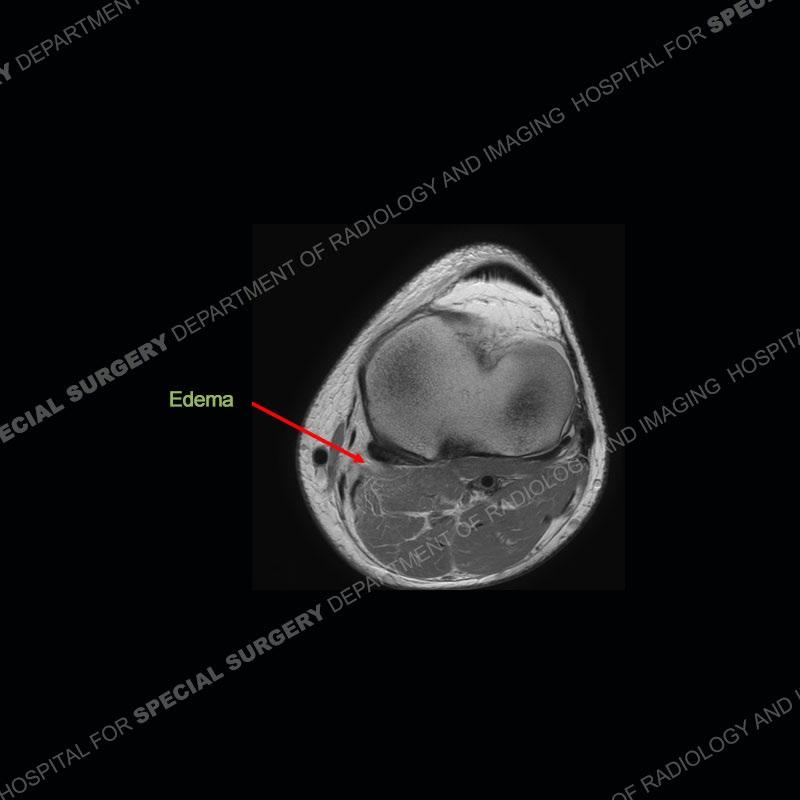

The radiographs show degenerative change of the medial compartment and a varus knee, but they are not germane to this case. No acute bony injury is present. The MRI shows edema of the posterior medial knee/soft tissue and a focal area of a partially disrupted low signal structure. The details are kept at a minimum in the findings of this case on purpose.

Diagnosis: Partial Disruption Medial Head Gastrocnemius (MHG)

The findings were kept purposefully vague as identifying the structures early on takes away a lot of the diagnosis. An uncommon entity and one of which we do not see a lot. Enthesopathic changes and tendinosis are seen as are distal MHG injuries, but proximal tears are rarely present. This case highlights a number of points. One, it almost always comes down to anatomy. Perhaps not a structure we normally spend too much time on, except save for diagnosing a Baker’s cyst, but knowing where this structure and all structures exist in all three planes is imperative. Second, when you think you are making a “call” or finding that you have never made before, step back and think is this just the abnormal presentation of a common pathology. That situation arises much more frequently. Third, if you look at it once, twice, and probably a third time and are confident in your odd or very rare diagnosis, stick to your guns. Especially, when it comes down to anatomic structures, the proof will be in the images.

Fourth, use all imaging planes and different pulse sequences to make your diagnosis. The edema highlighted in this case can be seen as the obscuration of fat on the PD images but is much easier to perceive as the high signal on the IR pulse sequences. The actual disruption of the MHG myotendinous junction is only able to be seen on the axial images. On the sagittal and coronal images, we get a sense something is wrong but hard to be exact. Lastly, when you look at a study and something just seems off (as I would say the sagittal and coronal images do with that dark band of tissue posteriorly), listen to yourself and go through the study slowly and meticulously. Most of the time you will find you were right, and something indeed is present.